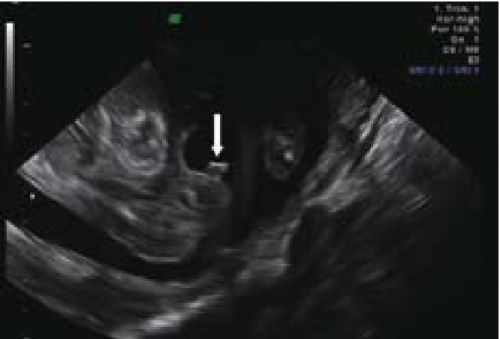

השתנה עוברית - 30 Vijayaraghavn דיווח על הדגמת השתנה עוברית גם בזכרים וגם בנקבות בשימוש באולטרסאונד רגיל וגם על ידי דופלר צבע. הדגמת מקור ההשתנה שימשה לאבחון שני עוברים עם היפוספאדיאס. שימוש Power Dopplerf עזר לנו לאבחן שלושה עוברים עם היפוספאדיאס, בשניים מהם הודגם מקור השתן מבסיס הפין ובשלישי מאמצע הפין. אולטרסאונד תלת מימדי - מנסיוננו, שימוש באולטרסאונד תלת מימדי אינו מוסיף משמעותית לאבחון מין העובר, במיוחד בטרימסטר הראשון ותחילת הטרימסטר השני ולעתים יכול אפילו להטעות (תמונה 6). 9Benoit ואחרים31,32 הגיעו למסקנה שאכן התלת מימד אינו עוזר לאבחון מין העובר אך השימוש בחתכים (sectional planes) לעתים יכול לעזור על ידי הצגת החתך הסגיטלי האמצעי ביתר קלות ובכך לעזור לאבחון מין העובר. בטרימסטר השני והשלישי התלת מימד יכול לעזור בהצגת איברי המין להורים בצורה יותר משכנעת (תמונות 7 ו-8). בחלק מהמקרים עם מומים באיברי המין החיצוניים, התלת מימד יכול להדגים את המום ולעזור להגיע לאבחנה, כפי שנדון בהמשך.

תמונה 8. איברי מין חיצוניים של נקבה בשבוע תמונה 9. תלת מימד של עובר עם היפוספאדיאס 32 בתלת מימד בשבוע 22. החץ מדגים הפין הזכרי המשוך כלפי מטה. S מדגים שק האשכים